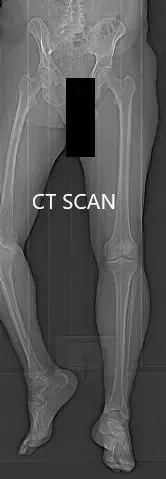

Se discutieron extensamente los riesgos, beneficios y alternativas. Se consideró candidata para una prótesis de rodilla personalizada. El paciente estuvo de acuerdo con el plan. Unas semanas antes se realizó una tomografía computarizada de las extremidades inferiores del paciente. La planificación precisa de los cortes y desplazamientos óseos fue posible gracias a los datos de la tomografía computarizada.

Imágenes topológicas de tomografía computarizada preoperatoria.